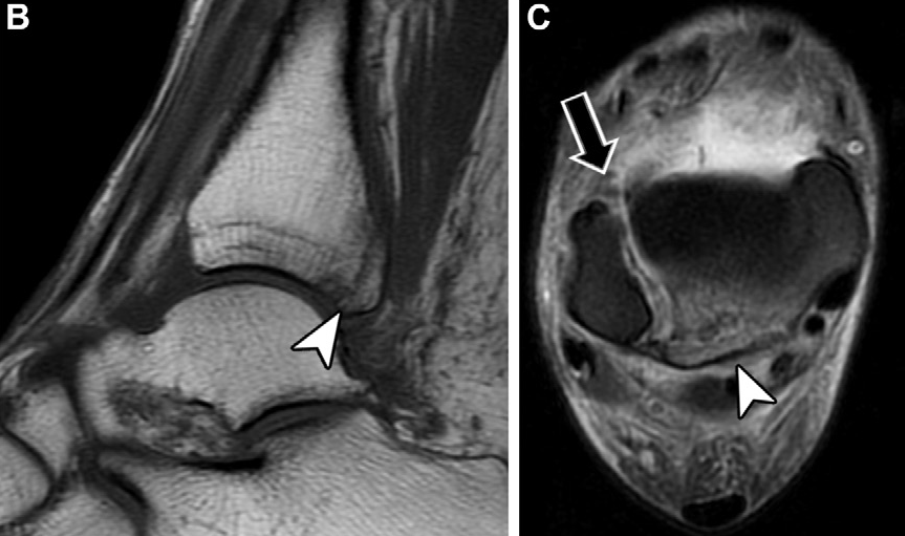

不稳定性损伤的MRI诊断要点

尽管MRI能精准评估韧带和骨性损伤,但无法对远端胫腓联合进行动态评估。因此,MRI可显示解剖学损伤,但不能直接确诊关节不稳,仅能通过间接影像学表现推断。MRI上提示胫腓联合不稳的关键征象包括:后下胫腓韧带完全撕裂、后踝骨折、三角韧带完全撕裂及胫腓联合近侧腓骨骨折。

下胫腓后韧带完全断裂是判断胫腓联合不稳的可靠指标,其敏感性为74%,特异性为 78%,阳性预测值为54%。后踝骨折对关节生物力学的影响与下胫腓后韧带完全断裂相当,且单独发生的概率极低,仅占所有踝关节骨折的1%~4%:

但该骨折常合并更复杂的损伤,包括双踝骨折、三踝骨折和腓骨近端骨折。约82%的Maisonneuve骨折患者会出现后踝骨折的症状和体征。尽管单纯三角韧带损伤通常为稳定性损伤,但当其与远端胫腓联合损伤并存时,会导致踝关节冠状面明显不稳。